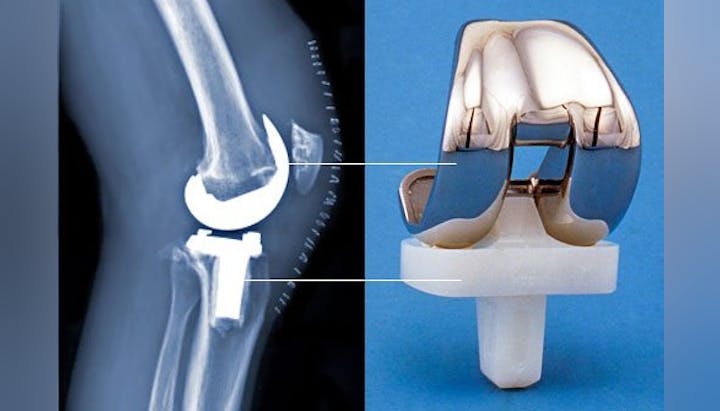

Home Beats Rehab for Knee, Hip Replacement Recovery

Can Dropping Some Weight Save Your Knees?